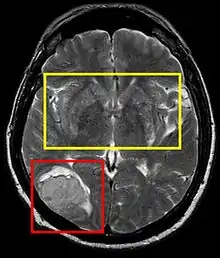

Stroke brain (similar to cerebral softening)

Cerebral softening, also known as encephalomalacia, is a localized softening of the substance of the brain, due to bleeding or inflammation. Three varieties, distinguished by their color and representing different stages of the disease progress, are known respectively as red, yellow, and white softening.[1][2]